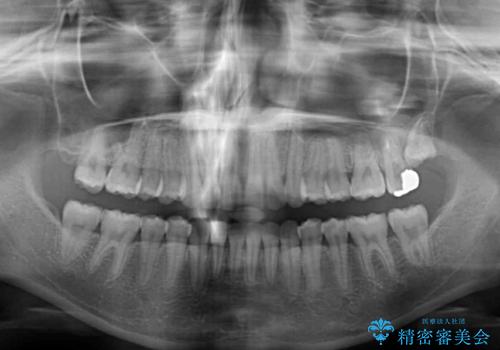

歯と歯の間を削ることで、飛び出した前歯が引っ込み、スッキリとした口元となりました。

歯の黄ばみも改善され、明るい歯並びとなりました。